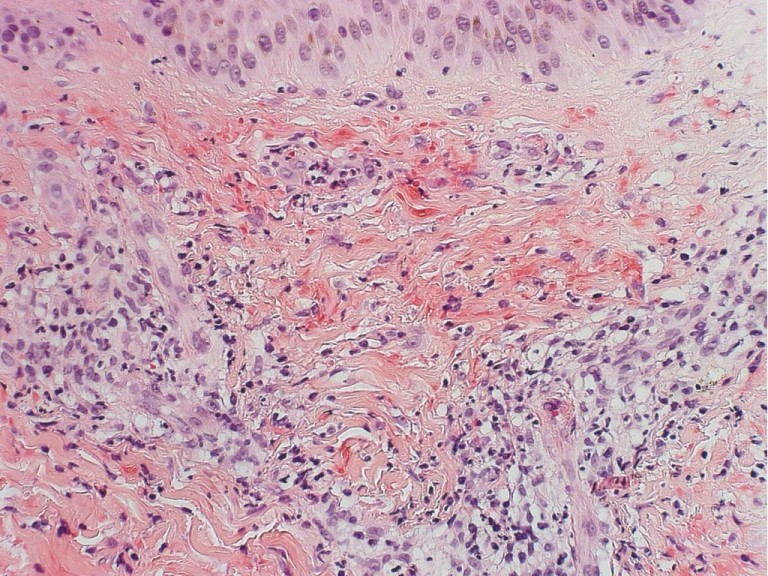

| leukocytoclastische vasculitis | leukocytoclastische vasculitis | leukocytoclastische vasculitis |